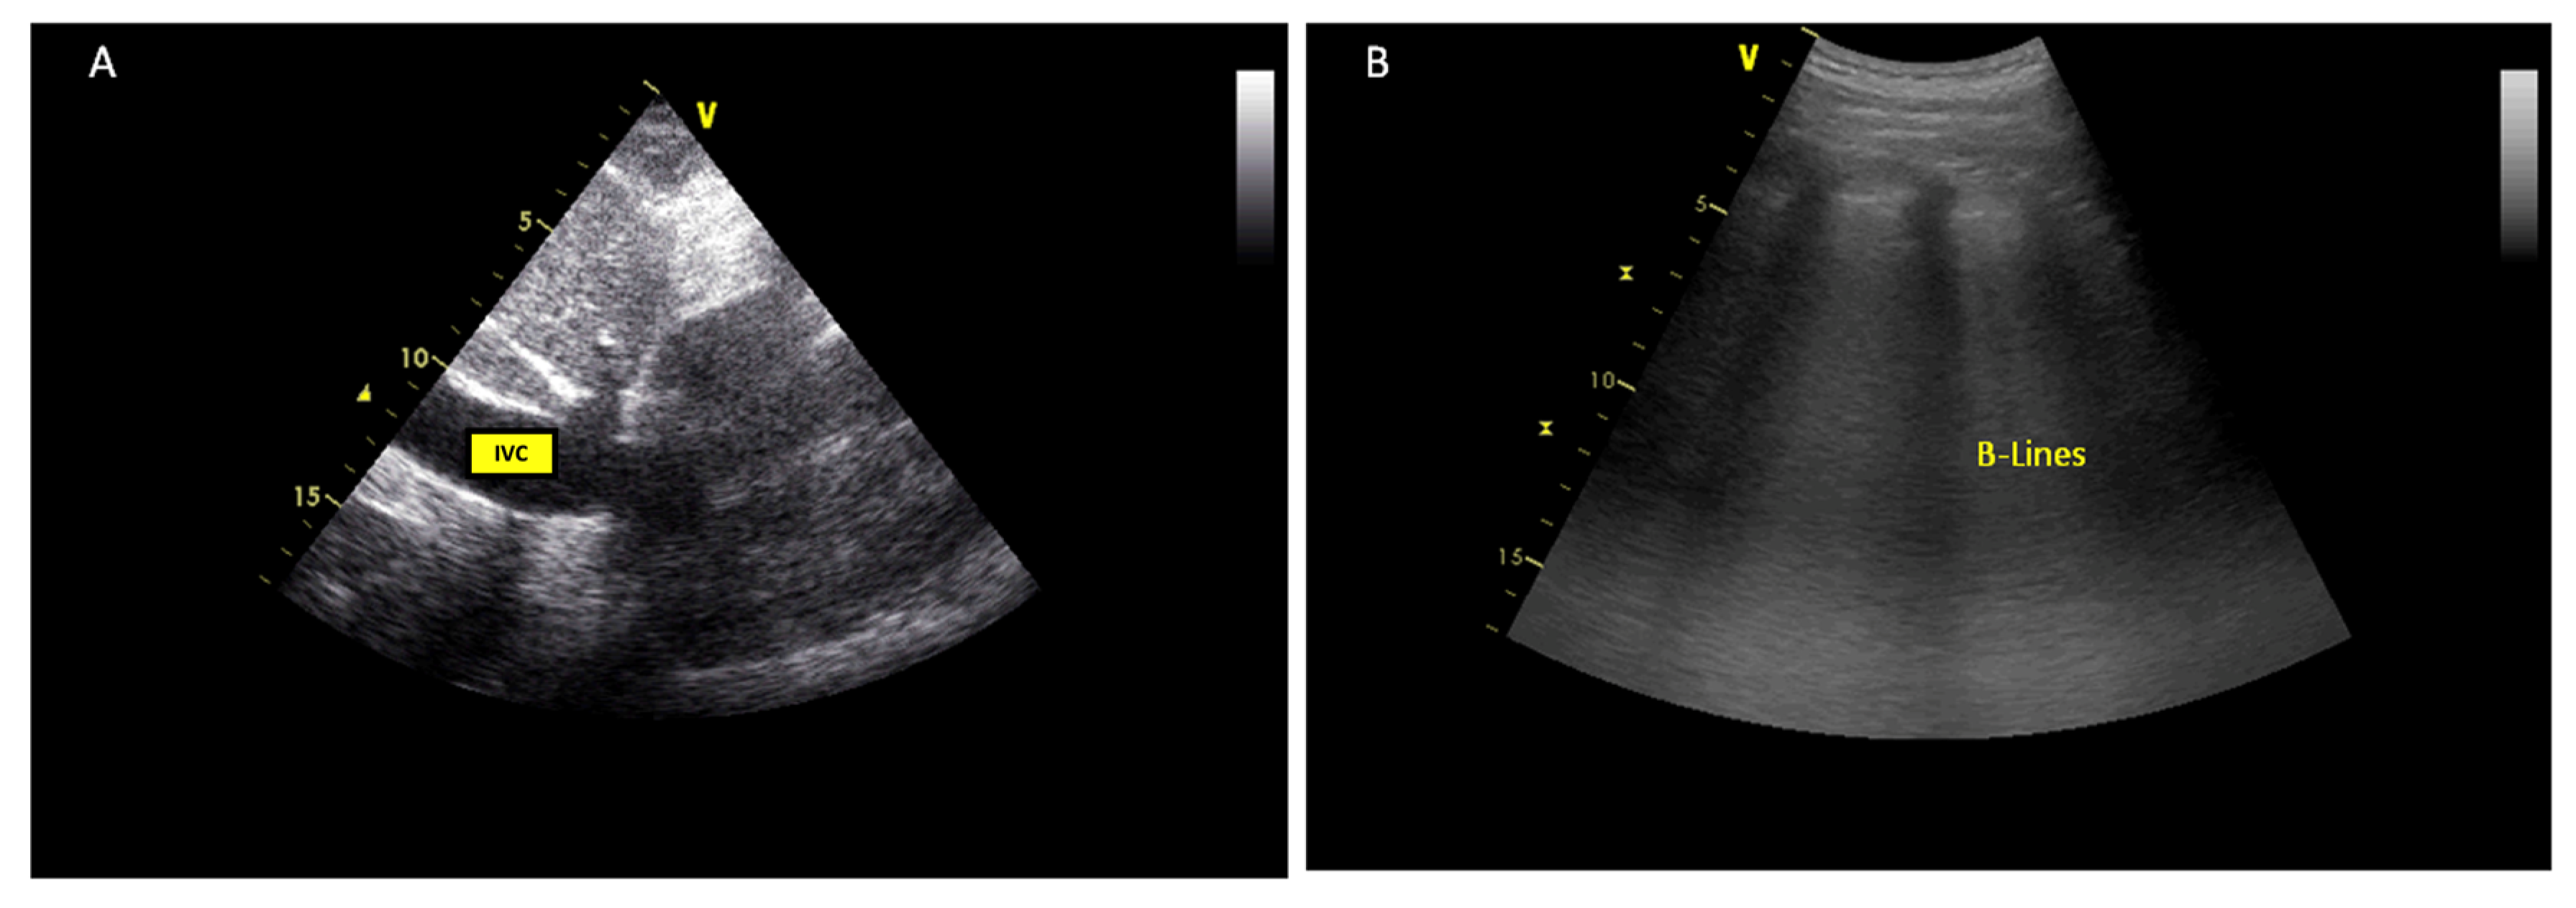

| Congestion parameters | IVC diameter | Used to estimate RA pressures | IVC < 21 mm that collapses > 50% |

| Grade 0 | IVC < 20 mm |

| Grade 1 | IVC ≥ 21 mm |

| Normal patterns or mild findings | |

| Grade 2 | IVC ≥ 21 mm |

| Severe finding in only one organ | |

| Grade 3 | IVC ≥ 21 mm |

| Severe findings in multiple organs | |